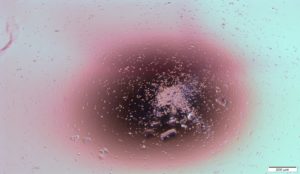

The immune response against viruses is initiated through recognition of viral molecules. The Cytokine network against viruses start with some cytokines produced by virus infected cells inducing a potent inflammatory response, attracting and activating phagocyte cells (e.g. neutrophils, macrophages, dendritic cells), mast cells and Natural Killer cells, to the site of infection. Furthermore, these cytokines are involved in the induction of an immune response with the purpose of eliminating infected cells and extracellular virus while other cytokines modulate the immune response.

Cytokines induce the expression of molecules cells promoting the recruitment of neutrophils and macrophages to the site of bacterial infection.

Cytokines are activated inducing and stimulating phagocytosis of neutrophils and macrophages.